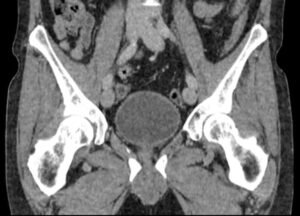

CT (computed tomography) scans are commonly used in the assessment of bone trauma due to their ability to provide detailed images of bones and surrounding